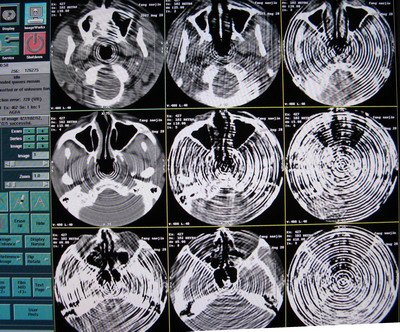

CT掃描圖像出現(xiàn)偽影,偽影圖像如下:

出現(xiàn)的頻率很高,且無規(guī)律,查看Error log,無報錯。